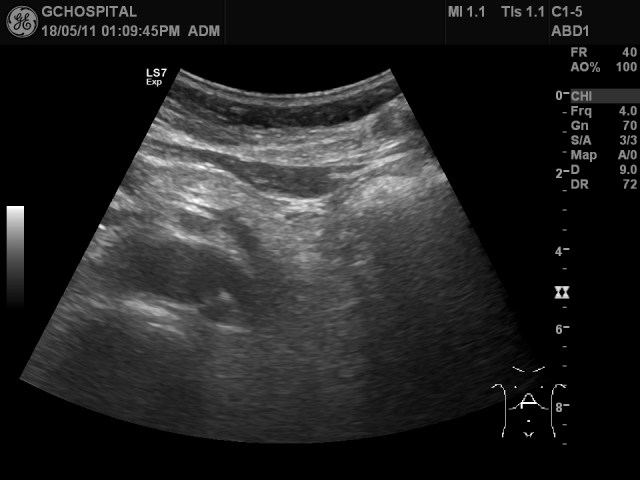

위 영상은 같은 시간이 지난 후에 다시 부른 후 환자의 자세를 semi-upright position으로 하고, 호홉을 조절하면서 다시 촬영한 영상입니다. 예전부터 보였던 췌장낭종을 선명하게 확인할 수 있습니다. 예전과 모양과 크기에 별다른 변화는 없었습니다.

췌장의 꼬리부위에서 의심스러웠던 저에코음영도 이번에는 전혀 보이지 않았으며, 전체적으로 균일한 에코음영의 췌장실질을 확인할 수 있었습니다.

이처럼, 췌장은 그때그때 환자의 컨디션이나 자세변화에 따라 다양한 인공물을 보일 수 있기에 촬영에 특히 주의해야 합니다. 췌장의 윤곽이 찍힌 사진을 한장 찍고 서둘러 끝낼 것이 아니라, 췌장의 머리쪽은 위아래부위 모두를 확인해야 하고(췌장낭종은 췌장 머리의 윗쪽에 위치하고 있었습니다) 췌장 내부에 병변이 있는것처럼 보이더라도, 항상 인공물의 가능성을 배제하지 않고 다른 자세나 각도에서 다시 한번 확인하는 습관을 들이는게 필요하다고 봅니다.